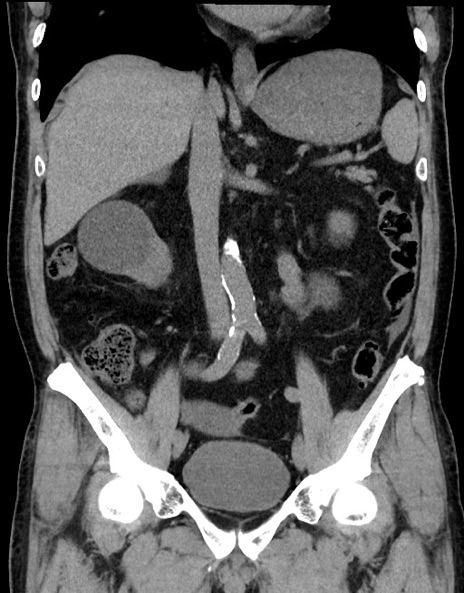

症例15(冠状断像)

【症例】70歳代男性

【主訴】腹痛

【現病歴】今朝から腹痛あり。全体的に痛い。特に左上の方。排ガスが今日はない。冷や汗が出る。

【既往歴】直腸癌術後

【身体所見】左側腹部〜上腹部に圧痛あり。腹膜刺激症状明らかなではない。軽度反跳痛。左下腹部に術後瘢痕あり。

【データ】WBC 7700、CRP 0.02